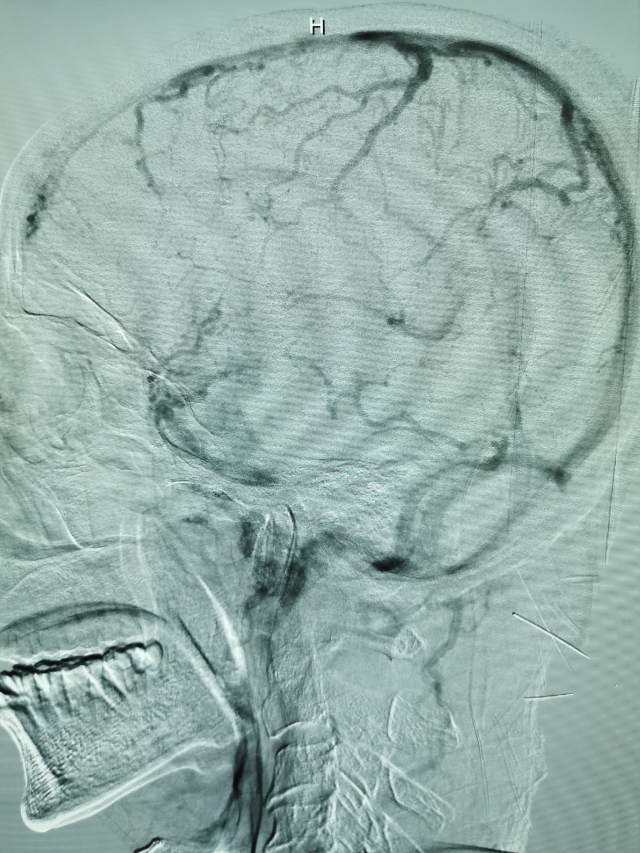

鉴于老人家体质虚弱,走路不方便,疫情期间,家人又不方便陪同,我们采用最微创的远侧桡动脉入路为老人家做了进一步检查,血管真的很扭哈,老人家也听不清楚,检查期间动来动去的,结果发现:下水道(深浅静脉系统有血栓堵塞)不通畅哦,次日给予了药物调整。治疗3天后,老人家听力明显改善,可以和医生自由交流,下床走路也如履平地,完全换了一个人哈~~~